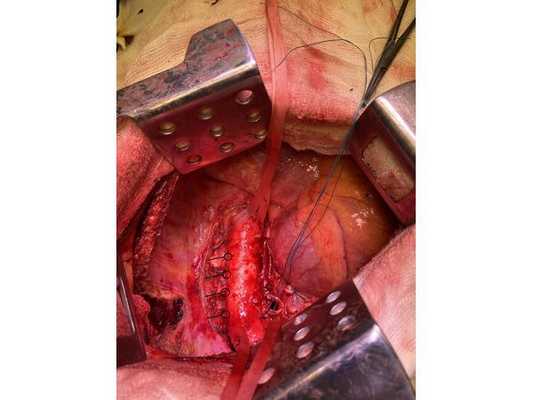

Интраоперационное фото: клипированные межрёберные артерии; аорта на тесёмочных держалках по краям зоны резекции адвентиции; культя главного бронха с провизорными швами при ушивании по Оверхольту

Проведён онкологический консилиум (Клиническая больница № 2 АО ГК МЕДСИ). Решением консилиума рекомендовано первым этапом провести хирургическое лечение в объёме нижней лобэктомии (удаления доли органа) с циркулярной резекцией левого главного бронха (удалением сегмента бронха с восстановлением целостности бронхиального дерева) или пневмонэктомии слева (полного удаления лёгкого) после интраоперационной ревизии с систематической медиастинальной лимфодиссекцией (иссечением лимфатических узлов).

- боковая торакотомия (вскрытие грудной клетки) слева;

- пневмонэктомия с резекцией адвентиции (наружной оболочки) аорты, париетальной и медиастинальной плевры и мышечной стенки пищевода;

- медиастинальная лимфаденэктомия.

1. В положении на правом боку с раздельной вентиляцией лёгких выполнена боковая торакотомия слева. При ревизии:

- в плевральной полости выпота (скопления жидкости) нет;

- имеются единичные сращения в области верхней доли и 6 сегмента — разделены при помощи электрокоагуляции;

- очагового поражения париетальной и висцеральной плевры нет.

- в нижней доле имеется плотная большая опухоль, подрастающая к грудной аорте и врастающая в медиастинальную плевру и средостение;

- сосуды корня лёгкого в опухолевый процесс не вовлечены;

- определяются множественные неувеличенные в размерах лимфатические узлы.

Учитывая данные интраоперационной ревизии, диагноз скорректирован: центральный местно-распространённый немелкоклеточный рак нижней доли левого лёгкого с врастанием в адвентицию аорты и ткани средостения — cT4NxM0. Принято решение о выполнении пневмонэктомии (полного удаления лёгкого).

2. Выделены и взяты на держалки верхняя и нижняя лёгочные вены, выделен ствол лёгочной артерии, который также взят на держалку. Выполнено пробное пережатие лёгочной артерии — нарушений гемодинамики (движения крови по сосудам) и гемоксигенации (насыщения крови кислородом) нет.

3. Последовательно прошиты сшивающими аппаратами и пересечены нижняя и верхняя лёгочные вены и ствол лёгочной артерии. Выявлено, что опухоль подрастает к мышечной стенке пищевода, выполнена краевая резекция мышечной стенки пищевода на протяжении 2 см.

4. Острым путём отсечён левый главный бронх, при этом обнаружено, что опухоль распространяется перибронхиально. Культя левого главного бронха реампутирована (ампутирована повторно) в пределах визуально здоровой ткани стенки бронха, до 1,5-2 см от карины трахеи (гребня хряща между разделением двух главных бронхов). Центральная часть культи левого главного бронха ушита по Оверхольту.

5. Отступив по грудной стенке от края врастания опухоли в аорты на 2 см, рассечена и отсепарована (отделена хирургически) париетальная плевра и адвентиция аорты. Аорта мобилизована по типу "ручки чемодана" и взята на тесёмочные держалки выше и ниже места врастания опухоли.

6. Скелетизируя грудную стенку и аорту, с перевязкой левых межрёберных артерий, на участке рёбер 4, 5, 6 и 7 выполнена полуциркулярная резекция адвентиции аорты, мягких тканей грудной стенки с париетальной плеврой и тканей средостения.

7. Пневмонэктомия. Проверка аэростаза (герметичности) под уровнем жидкости — просачивания воздуха в области культи бронха нет.

8. Выполнена лимфодиссекция из области лёгочной связки, области бифуркации трахеи (места её разделения на главные бронхи), аортального окна, левого трахеобронхаильного угла и нижних паратрахеальных лимфатических узлов слева. Проверка гемостаза — сухо.

10. В плевральную полость заведён толстый силиконовый дренаж. Послойное ушивание раны, рёбра сведены тремя перикостальными швами. Наложена асептическая повязка.